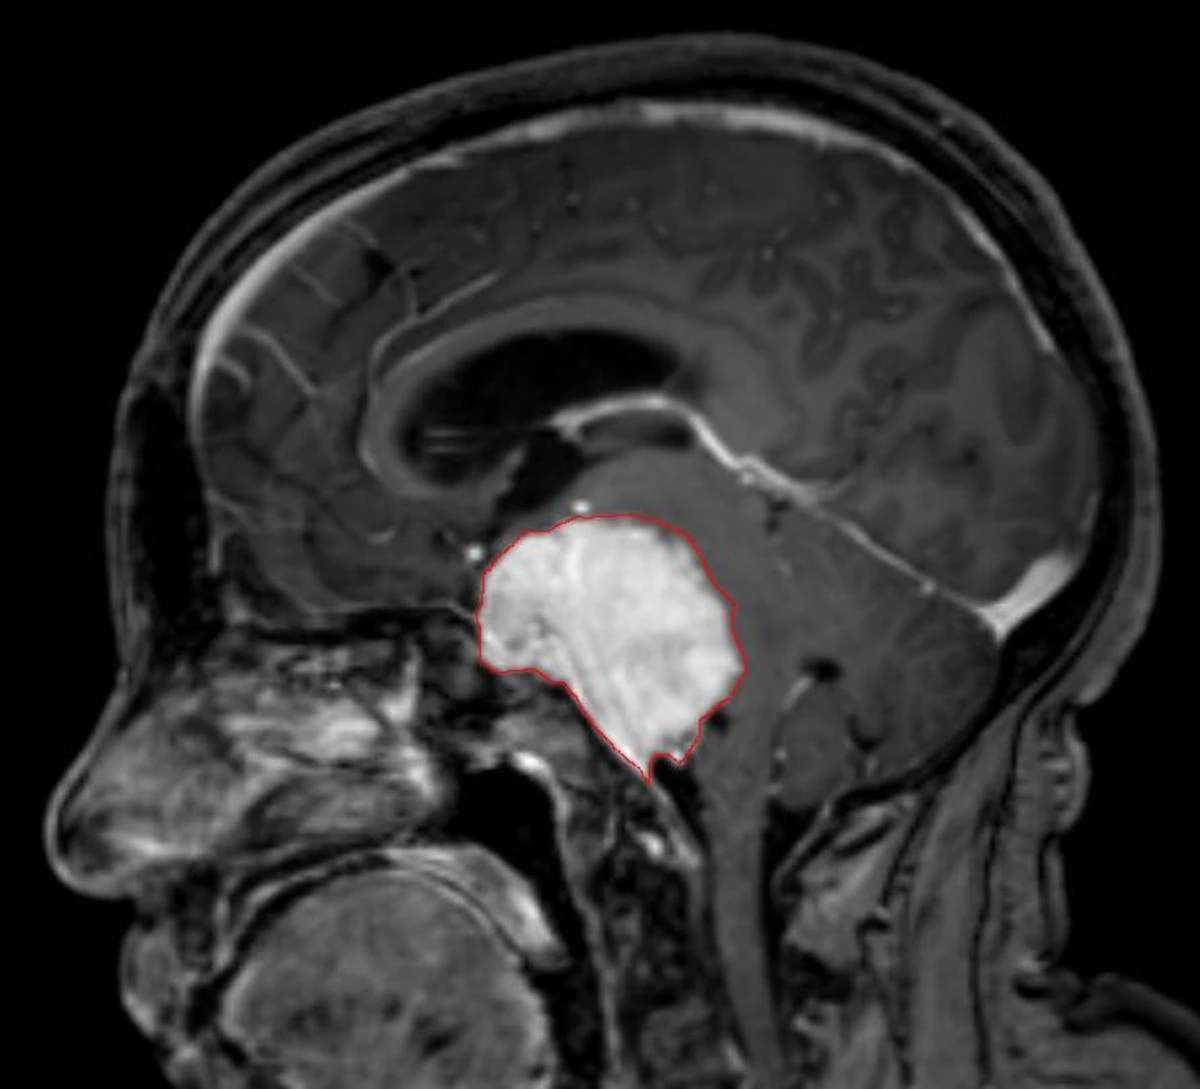

La diagnosi di meningioma si basa su esami di imaging, con particolare riferimento alla risonanza magnetica che consente di valutare le dimensioni, la posizione e le caratteristiche della lesione. In presenza di un tumore di piccole dimensioni e privo di sintomi evidenti, può essere indicato un monitoraggio periodico per verificare l’eventuale crescita. Nei casi in cui il meningioma provochi disturbi significativi o sia localizzato in aree critiche, il trattamento può prevedere un intervento chirurgico, eventualmente seguito da radioterapia se la rimozione completa non è possibile.